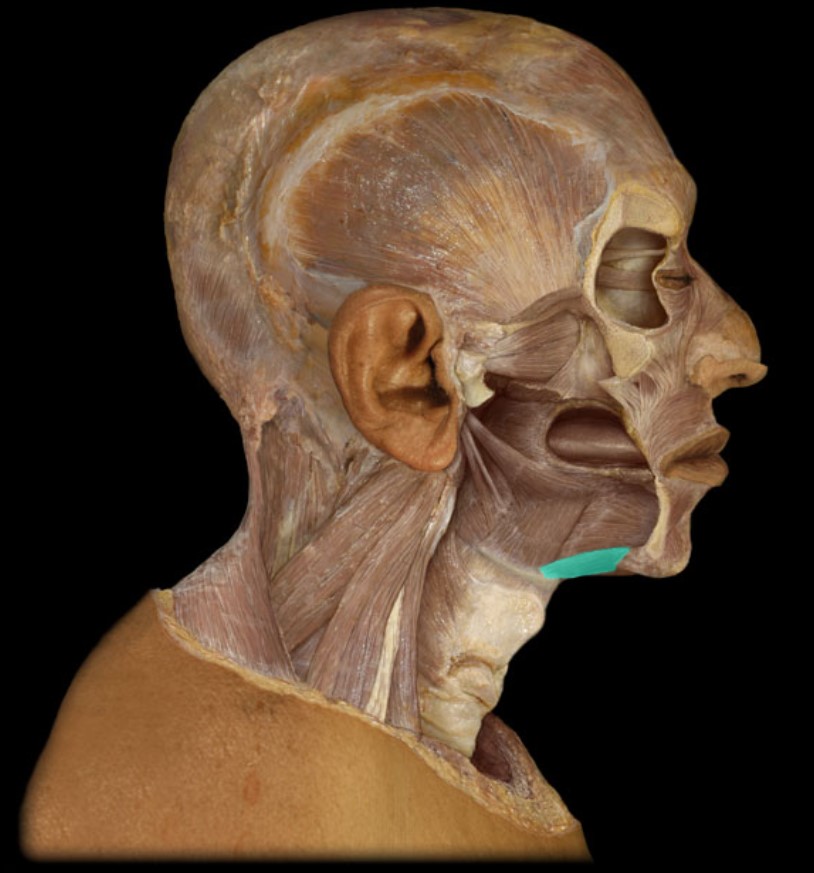

Mandible

Mylohyoid

Geniohyoid

Hyoid